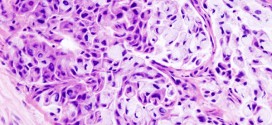

El Colangiocarcinoma de la vesícula biliar. Tumor maligno en general de las vías biliares. El sistema para drenar la bilis, incluye los conductos o vías extrahepático, conductos biliares intra y la vesícula biliar. Son como una red de cañerías, llamados conductos que están conectados con la vesícula biliar, el intestino delgado y el hígado. El Colangiocarcinoma este tumor se ubica …